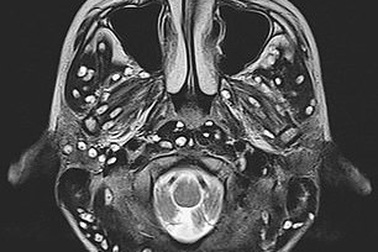

Sán làm tổ trong não vì 3 món nhiều người Việt thường ănChụp cộng hưởng từ sọ não thấy khối tổn thương ký sinh tại vùng não của bệnh nhân do ấu trùng sán dây lợn.

Ổ sán chi chít trong não người đàn ông vì món nhậu "giải đen"Kiêng món này nhiều năm, bệnh nhân vẫn không thể thoát khỏi di chứng và những cơn đau đầu, co giật, sùi bọt mép.

Rùng mình với ấu trùng sán chi chít trong não do ăn thịt lợn chưa nấu chínMột nam thanh niên 18 tuổi sống ở Ấn Độ đã tử vong do nhiễm ấu trùng sán trong não sau khi ăn thịt lợn chưa nấu chín.